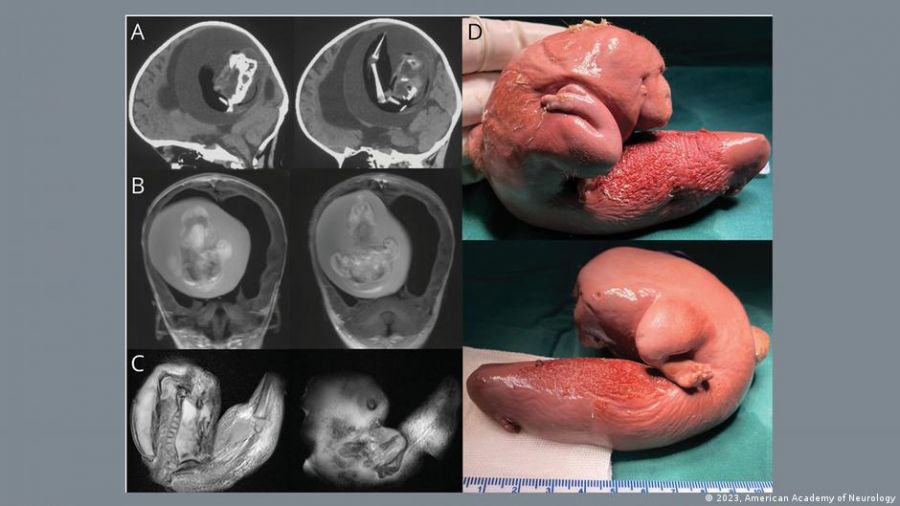

Imagen real del caso ocurrido en China conocido como la anomalía "feto en feto".

Al realizarse la intervención quirúrgica, se pudo observar que el feto del "gemelo parásito” mostraba indicios claros de desarrollo: columna vertebral, dos huesos de la pierna (fémur y tibia), además de dedos en las extremidades superiores. Además, se identificó que sufría de espalda bífida (cuando parte de la médula espinal queda expuesta).